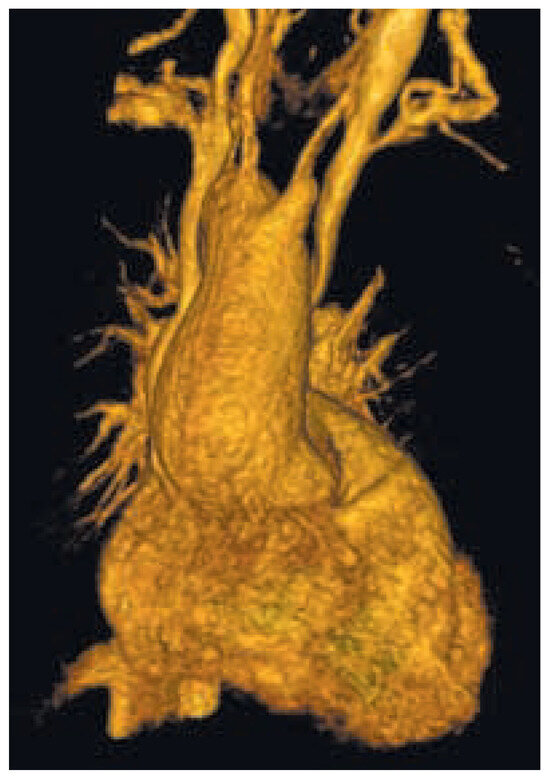

Une patiente de 31 ans souffrant d’une cardiopathie congénitale consulte car elle souhaite une grossesse [...]